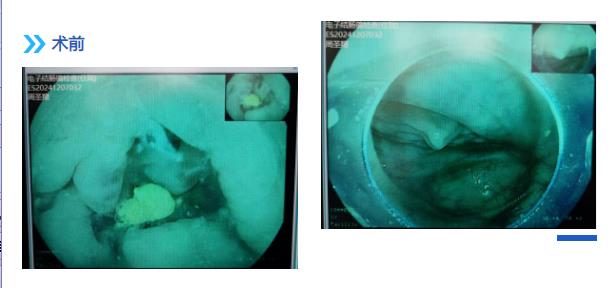

退镜观察见阑尾开口呈半月形,回盲瓣唇型、光滑,通过活检孔道送入一次性成像导管, 后寻腔将一次性成像导管送入阑尾腔,腔内可见多块成形粪石,使用一次性内镜取石网篮粉碎取出多块粪石,应用生理盐水冲洗阑尾开口可见粪石流出,同时可见絮状脓性分泌物流出,后反复观察阑尾腔内,无明显粪石存留,阑尾腔内管壁局灶略粗糙充血发红,近阑尾口处为著。余所见肠腔通畅,肠瓣形态正常,粘膜光滑,无充血水肿, 血管网清晰,未见糜烂、溃疡、息肉、瘢痕及新生物。